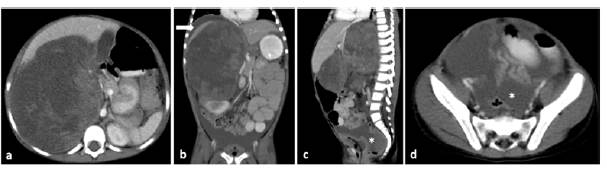

Signs of tumor rupture were found in the imaging studies of 13 Wilms tumors (presence of free fluid in the cul-de-sac, perirenal fat stranding, and presence of retroperitoneal free fluid). Such signs were not observed in the non-Wilms tumors group. Tumor rupture was reported intraoperatively in 6 tumors, all of them with imaging signs of rupture Figure 3.

Imaging findings of tumor rupture in a 4-year-old female patient with a perioperative Wilms tumor rupture. Contrast-enhanced CT scan of the abdomen, axial (a and d), coronal (b) and sagittal planes (c), showing a solid mass with a tumor size >10cm and volume >1000cc in the right kidney. Imaging signs of rupture: fat stranding, presence of free perirenal fluid (white arrow in b) and of free fluid in the pelvic cavity and the cul-de-sac (asterisk in c and d).

Figure 3: Imaging findings of tumor rupture in a 4-year-old female patient with a perioperative Wilms tumor rupture. Contrast-enhanced CT scan of the abdomen, axial (a and d), coronal (b) and sagittal planes (c), showing a solid mass with a tumor size >10cm and volume >1000cc in the right kidney. Imaging signs of rupture: fat stranding, presence of free perirenal fluid (white arrow in b) and of free fluid in the pelvic cavity and the cul-de-sac (asterisk in c and d).

Source: Picture Archiving and Communication System of the Radiology Service of the Fundación Hospital Pediátrico La Misericordia.

The characteristics of the 41 Wilms-tumors, classified according to the surgical confirmation of tumor rupture, as well as the results of the univariate analysis carried out to assess the association between tumor variables (tumor size, volume and type) and peri-operative rupture are shown in Table 3. Tumor volume was associated with a higher risk of tumor rupture (OR: 3.08, 95%CI: 1.04-9.09; p<0.05).